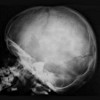

Рентгенография черепа ребенку

Рентгенография черепа ребенка широко применяется в практике детской неврологии и нейрохирургии, детской травматологии. Показаниями к рентгенографии черепа ребенка могут быть врожденные дефекты черепной кости, гидроцефалия, микроцефалия, родовые травмы, мягкая головная гематома, внутричерепная гипертензия, несоответствие или ранний анастомоз черепных швов, ЧМТ, опухоли гипофиза Рентгенография черепа ребенка обычно выполняется в прямой проекции и боковой (при необходимости, осевой, полуосевой ). При анализе черепа ребенка внимание уделяется форме и размеру черепа; границы, структура и толщина отдельных костей; состояние черепных швов и пружин, паттерн кровеносных сосудов и паттерн «пальцевых нажатий»; дыры в костях черепа, глубина дна черепа, турецкое седло.